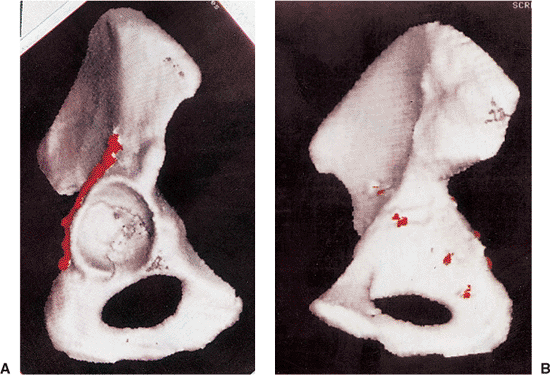

accident, sustaining an atypical T-shaped fracture of the acetabulum

with intra-articular comminution (Figs. 41.46, 41.47 and 41.48).

ORIF was advised because of the instability and incongruency of the hip

joint. Surgery was performed 4 days after injury by using the

Kocher-Langenbeck approach (Figs. 41.49, 41.50, 41.51 and 41.52).

One week later, the patient was discharged to home from the hospital

with instruction to proceed with toe-touch weight bearing with crutches.

Figure 41.48. Preoperative three-dimensional CT, showing the external (A) and endopelvic (B) aspects. An atypical T-shaped pattern with intra-articular comminution is demonstrated.

Figure 41.51. A,B. Postoperative two-dimensional CT sections corresponding to the levels of the preoperative samples shown in Figure 41.47.

Figure 41.52. A,B. Postoperative three-dimensional CT with fixation highlighted in red.